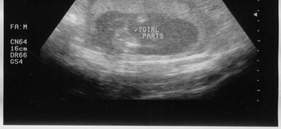

Second Sonogram, taken 04-22-02.